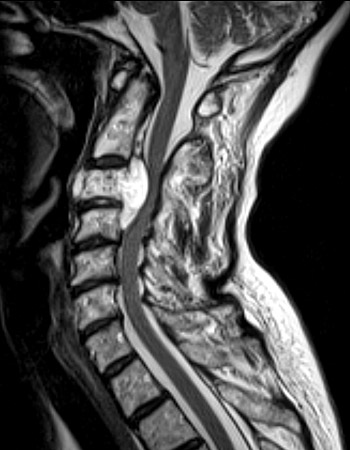

The sagittal MRI scan above demonstrates a

destructive mass

which is a chordoma that is destroying the C2 vertebral body and

impinging upon the spinal cord

. Another sagittal view with T2 weighting, and an axial view appear below.